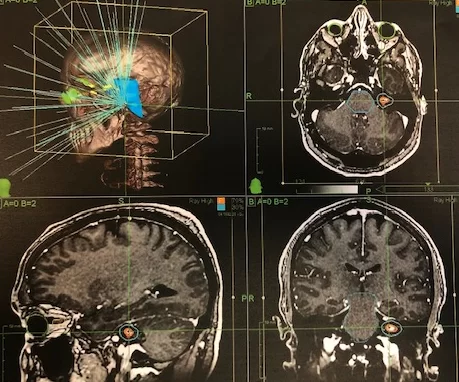

Λόγω της συμπτωματικής βλάβης με αύξηση του μεγέθους της, αποφασίστηκε πλέον αντιμετώπισή της. Συνυπολογίζοντας το μέγεθος και τη θέση του νευρινώματος, προκρίθηκε ως καταλληλότερη θεραπεία η ακτινοχειρουργική.

Η σταδιακή αύξηση του μεγέθους του νευρινώματος σε συνδυασμό με τα συμπτώματα υποστηρίζουν την απόφαση για αντιμετώπιση. Εδώ η ακτινοχειρουργική είναι η ιδανική λύση μια και προσφέρει πολύ καλά αποτελέσματα ελέγχου της βλάβης με υψηλό προφίλ ασφαλείας. Η αντιμετώπιση τέτοιων περιστατικών προϋποθέτει καλή συνεργασία ανάμεσα στο νευροχειρουργό και τον ακτινοθεραπευτή αλλά και σωστή, ειλικρινή ενημέρωση του ασθενούς για τα αποτελέσματα της θεραπείας.